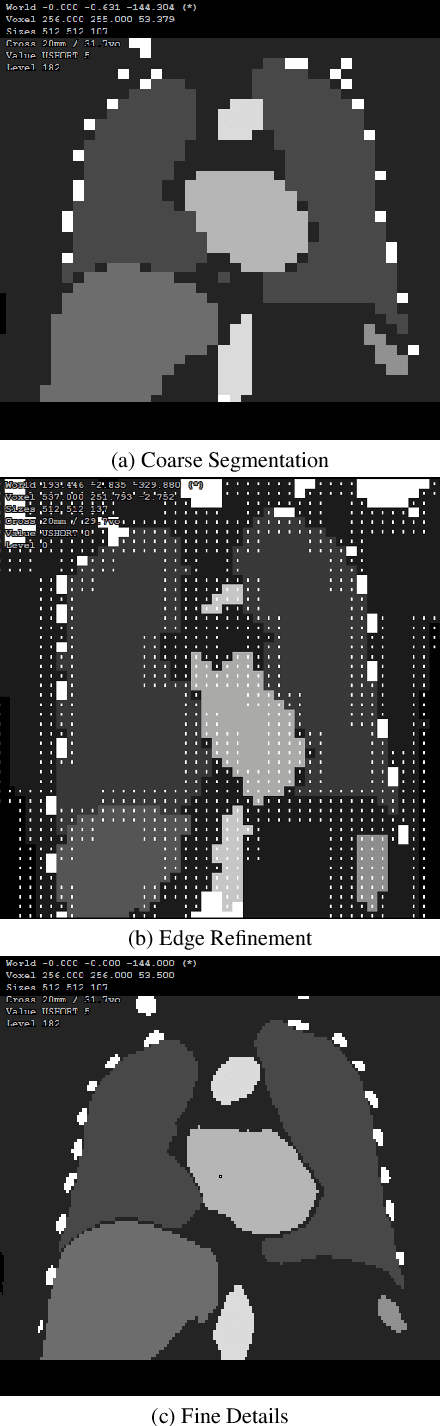

Abstract:Multi-organ segmentation of 3D medical images is fundamental with meaningful applications in various clinical automation pipelines. Although deep learning has achieved superior performance, the time and memory consumption of segmenting the entire 3D volume voxel by voxel using neural networks can be huge. Classifiers have been developed as an alternative in cases with certain points of interest, but the trade-off between speed and accuracy remains an issue. Thus, we propose a novel fast multi-organ segmentation framework with the usage of hierarchical sparse sampling and a Residual Transformer. Compared with whole-volume analysis, the hierarchical sparse sampling strategy could successfully reduce computation time while preserving a meaningful hierarchical context utilizing multiple resolution levels. The architecture of the Residual Transformer segmentation network could extract and combine information from different levels of information in the sparse descriptor while maintaining a low computational cost. In an internal data set containing 10,253 CT images and the public dataset TotalSegmentator, the proposed method successfully improved qualitative and quantitative segmentation performance compared to the current fast organ classifier, with fast speed at the level of ~2.24 seconds on CPU hardware. The potential of achieving real-time fine organ segmentation is suggested.

Abstract:Organ segmentation is a fundamental task in medical imaging, and it is useful for many clinical automation pipelines. Typically, the process involves segmenting the entire volume, which can be unnecessary when the points of interest are limited. In those cases, a classifier could be used instead of segmentation. However, there is an inherent trade-off between the context size and the speed of classifiers. To address this issue, we propose a new method that employs a data selection strategy with sparse sampling across a wide field of view without image resampling. This sparse sampling strategy makes it possible to classify voxels into multiple organs in real time without using accelerators. Although our method is an independent classifier, it can generate full segmentation by querying grid locations at any resolution. We have compared our method with existing segmentation techniques, demonstrating its potential for superior runtime in practical applications in medical imaging.